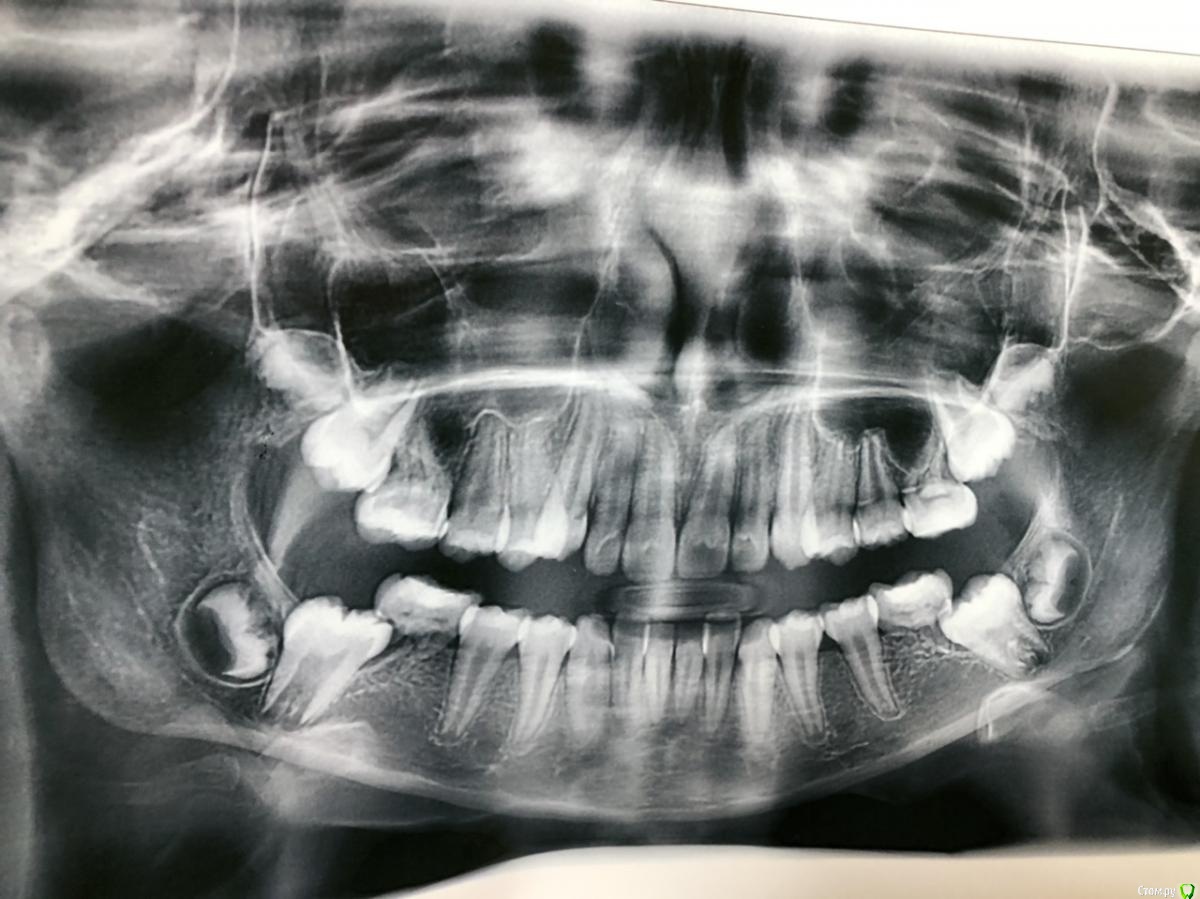

Basya Опубликовано 11 февраля, 2021 Поделиться Опубликовано 11 февраля, 2021 Здравствуйте! Ребёнку 11лет, беспокоили нижние шестёрки при приеме пищи. Сделали снимок и на сколько я вижу-корней нет у всех шестых зубов? Посмотрите, пожалуйста, на сколько всё плохо? Ссылка на комментарий

Марья Моревна Опубликовано 11 февраля, 2021 Поделиться Опубликовано 11 февраля, 2021 (изменено) Это похоже на пятые молочные с резорбированными корнями. Изменено 11 февраля, 2021 пользователем Марья Моревна Ссылка на комментарий

Basya Опубликовано 11 февраля, 2021 Автор Поделиться Опубликовано 11 февраля, 2021 Это шестёрки (на сколько я считать умею). Имеется скученность передних зубов, может по снимку не четко понятно. Ссылка на комментарий

Zlata-doctor Опубликовано 12 февраля, 2021 Поделиться Опубликовано 12 февраля, 2021 это не молочные зубы, но резорбция корней налицо. Скорее всего, это врожденная аномалия. Надо уточнить диагноз, конечно. Но я бы думала в сторону удаления шестерок, пока ребенок не повзрослел и семерки легче встанут на их место. Скорее всего , потребуется помощь ортодонта. 3 Ссылка на комментарий

red_butler Опубликовано 12 февраля, 2021 Поделиться Опубликовано 12 февраля, 2021 Доброе утро, спасибо за ответ.Подскажите, резорбция корней у всех шестёрок? Это 4 постоянных зуба под удаление?у всех, меньше всего на верху справа Ссылка на комментарий

Zlata-doctor Опубликовано 12 февраля, 2021 Поделиться Опубликовано 12 февраля, 2021 Да, по моему мнению все на удаление.Это будет лучше, чем потерять зуб в более зрелом возрасте. Ссылка на комментарий

Марья Моревна Опубликовано 14 февраля, 2021 Поделиться Опубликовано 14 февраля, 2021 Есть две тактики : держать место, пока ребенок растет, потом сделать имплантацию; или двигать семерки ортодонтически.Обсудите со своим ортодонтом. Удалять лучше, когда определитесь. Ссылка на комментарий

Zlata-doctor Опубликовано 15 февраля, 2021 Поделиться Опубликовано 15 февраля, 2021 Удаление всех четырёх для того, что бы с помощью ортодонта закрыть дыры оставшимися зубами и жить с комплектом отставших зубов? Какие в этом случае будут минусы, проблемы? Извините, если я неграмотно вопросы задаю и глупости спрашиваю.Да, но нужен квалифицированный ортодонт. Первые моляры ( шестерки) являются ключами окклюзии ( по ним выстраиваются следующие зубы.) Минус один- поиск квалифицированного ортодонта. Не удаляйте пока не найдете такого. 1 Ссылка на комментарий